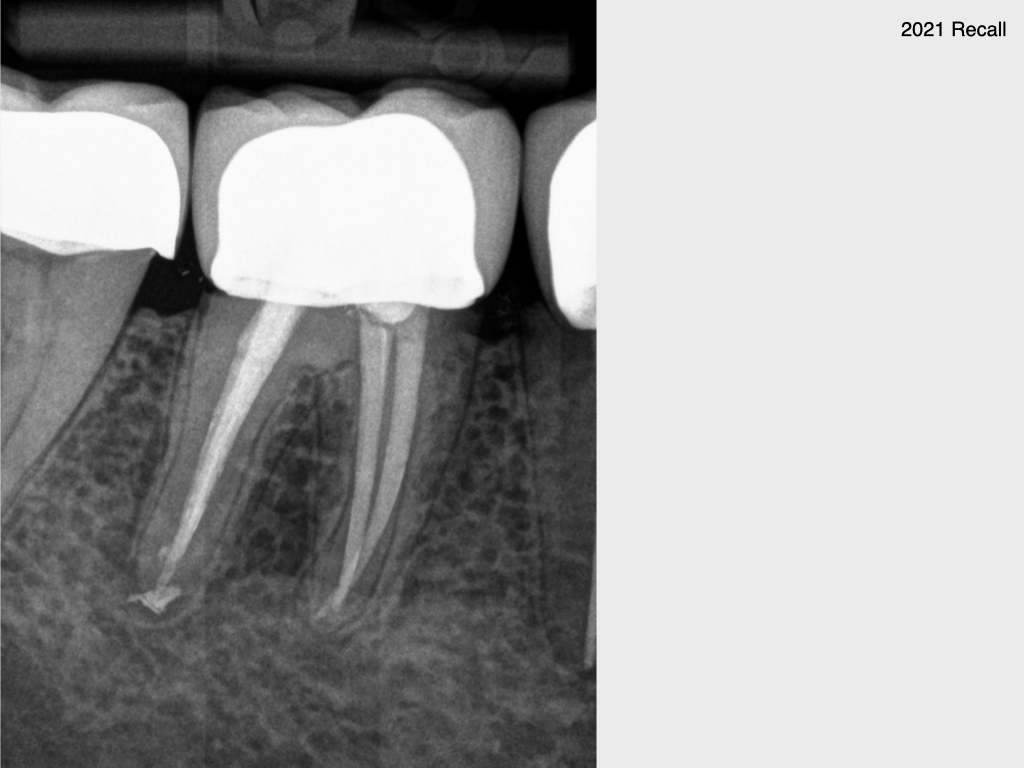

9647.005 Veröffentlicht 2. November 2021 am 1024 × 768 in Erst hatte er kein Glück und dann kam auch noch Pech dazu…